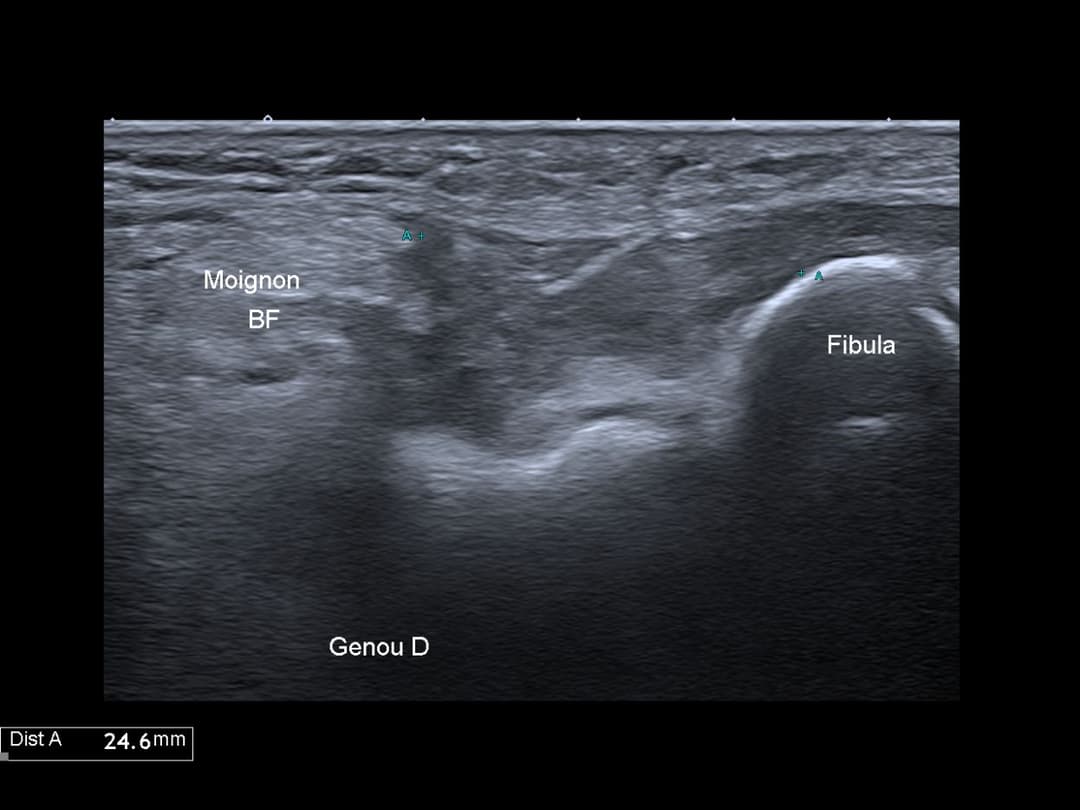

Echographie réalisé avant chirurgie pour marquage du nerf fibulaire commun.

Désinsertion avec rétraction de 2.5 cm de l'insertion fibulaire du ligament collatéral latéral et du tendon biceps fémoral.

Désinsertion complète du LCL et du tendon biceps fémoral

Visualisation du moignon distal du NFC